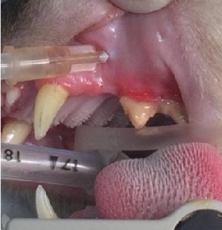

치조골 삭제

발치후 봉합